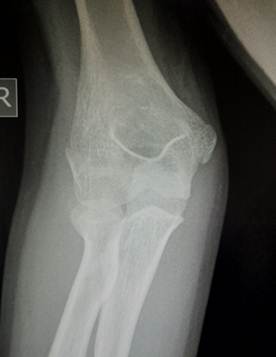

11- 13 лет

Это возраст, в котором все ядра окостенения достигли максимального

развития и приняли формы соответсвующих образований. На рентгенограммах их

разделяют узкие полоски ростковых зон. Это максимальный расцвет детского локтя.

Возраст

12 лет. Все ядра окостенения локтя развиты и разделены узкими хрящевыми

прослойками. Вершина локтевого отростка содержит основное ядро окостенения и

ядро – спутник неправильной формы.

14 лет. Стремительное закрытие зон роста локтевого сустава. Можно заметить

узкие просветы в основании медиального и латерального надмыщелков, а также пока

еще открытую зону роста в локтевом отростке.

Иногда

трудности с интерпретацией рентгенологической картины локтевого сустава

возникают даже у многоопытных специалистов. И что тогда делать? – Надо сделать

рентгенограммы противоположного, здорового сустава и сравнить. Но в большинстве

случаев внимательное изучение анамнеза, клинической картины и рентгенограммы

позволяет принять правильное решение и без этого.